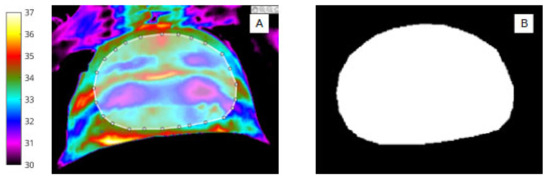

The manual segmentation procedure was performed in MATLAB (R2020a: Mathworks). The image labeller application was used to annotate each ROI label via pixel-level segmentation and creation of pixel masks for the series of 50 abdominal (Figure 1) and wound sites (Figure 2). The segmentation process was performed by two independent researchers, ‘blinded’ to the segmentation process of the other, and was broadly achieved in two stages to

Figure 2.

(A) Infrared image showing segmentation of the abdomen (ROI 1) and white bounding box. (B) Binary mask of abdomen (ROI 1).

For abdomen (Figure 2A,B) and wound segmentation (Figure 3A,B), the respective regions were identified in infrared and the ROI was selected and cropped. With respect to the surgical site, ROI 2, determining the extent of the area, was often difficult to identify in infrared due to lack of clear anatomical landmarks. To help discern wound area from surrounding healthy skin, reference was made to the corresponding digital image.